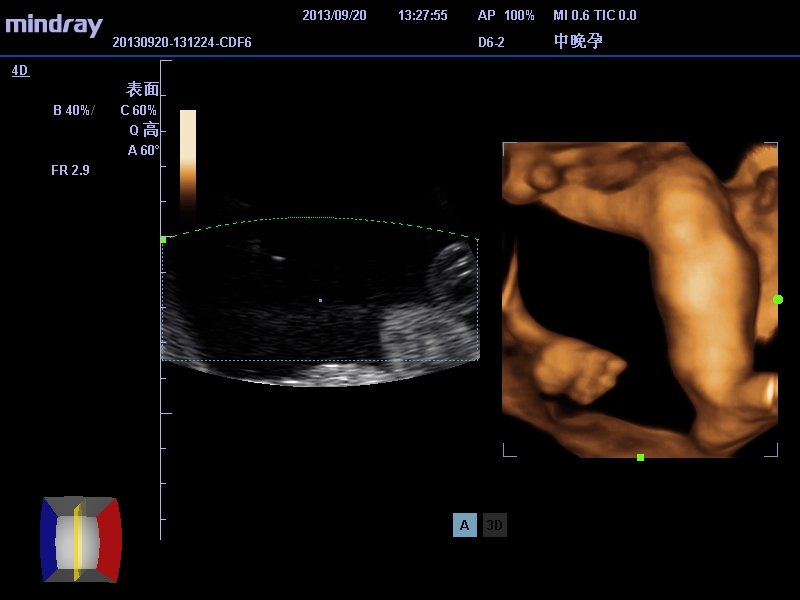

有医生可以帮我看看做四维彩超拍到了像是男孩的生殖器

请医生帮我看看这是男性的生殖器吗   是不是男孩啊

不得不说这技术看着让人揪心,二维只能肯定脐带影像,三维像是腿的部分,至于你说的生殖报揭器没法认定。再说现在禁细沃贵止鉴定胎儿性别,男孩女孩不一样好么?何况超声所见也有假阴性和假阳性,只能命竖生下来了才最终揭晓。